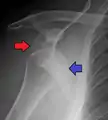

A diagnosis of shoulder dislocation is often suspected based on the person's history and physical examination. Radiographs are made to confirm the diagnosis. Most dislocations are apparent on radiographs showing incongruence of the glenohumeral joint. Posterior dislocations may be hard to detect on standard AP radiographs, but are more readily detected on other views. After reduction, radiographs are usually repeated to confirm successful reduction and to detect bone damage. After repeated shoulder dislocations, an MRI scan may be used to assess soft tissue damage. In regards to recurrent dislocations, the apprehension test (anterior instability) and sulcus sign (inferior instability) are useful methods for determining predisposition to future dislocation.

Posterior (backward)

Posterior dislocations are uncommon, and are typically due to the muscle contraction from electric shock or seizure.[6] They may be caused by strength imbalance of the rotator cuff muscles. People with dislocated shoulders typically present holding their arm internally rotated and adducted, and exhibiting flattening of the anterior shoulder with a prominent coracoid process.

Posterior dislocations may go unrecognized, especially in an elderly person[12] and in people who are in the state of unconscious trauma.[13] An average interval of 1 year was noted between injury and diagnosis in a series of 40 people.[14]